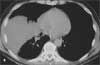

During the evaluation of a 61-year-old man who had sustained mild head and upper trunk injuries in a car accident, a right lower lobe consolidation was noted on the chest radiograph. There was no evidence of rib fracture. A chest CT scan with contrast showed a hilar mass that obstructed the lateral segmental bronchi of the right lower lobe (A, arrow). Atelectasis of the posteromedial segments of the right lower lobe and ipsilateral subcarinal adenopathy were also noted (B).

The patient had a 60 pack-year smoking history. For the past 4 days, he had had flu-like symptoms but considered himself generally healthy. He took no medications. Except for decreased air entry over the right lower lung field, vital signs and physical findings were normal.

The CT findings along with the history of heavy smoking raised the suspicion of lung cancer, and bronchoscopy with multiple transbronchial biopsies was performed. Histopathological examination showed chronic submucosal inflammation and clusters of microorganisms with sulfur granules; these findings were consistent with Actinomyces infection.